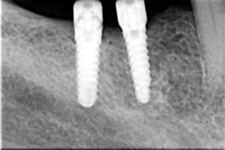

Bezzubá čelist je hlavní indikací pro ošetření pomocí implantátů. Zejména celkové zubní náhrady v dolní čelisti mají velice nízkou stabilitu a držení díky velkému úbytku kosti.

S pomocí zubních implantátů můžeme díky různým kotevním systémům (třmeny, kulové hlavy, Locatory) zajistit stabilitu a držení protézy nebo při použití většího počtu implantátů zhotovit pevné náhrady – můstky nalepené nebo našroubované na pevno na implantáty.